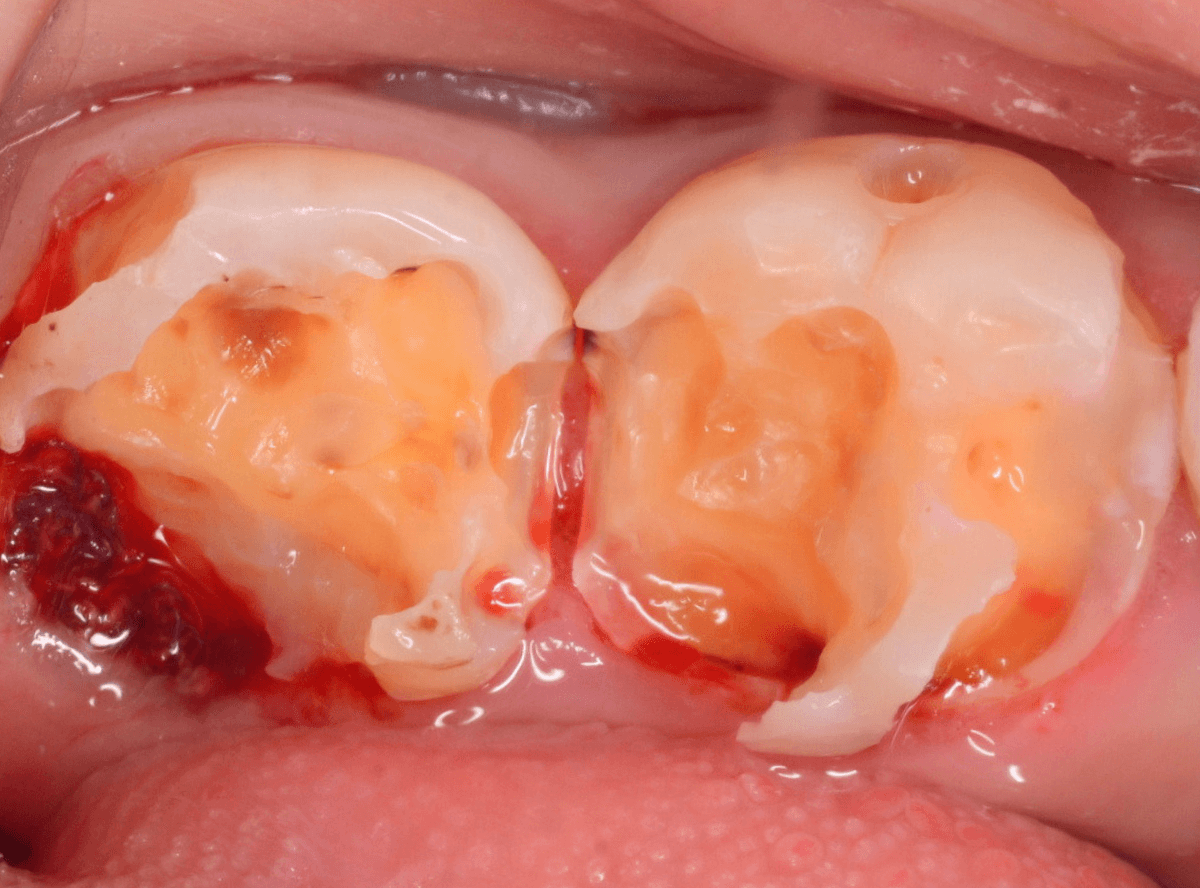

麻酔をして、治療を開始します。

レジンを外すと、中から出血してきました。

これは、歯のスキマに歯肉が入り込んでしまったために起こってしまったものです。

おそらく、随分前から虫歯が進行していたと思われます。

止血しながら、電気メスで歯の中に入り込んだ歯肉を除去します。

虫歯と入り込んだ歯肉でぐちゃぐちゃになっている状態でした。

慎重に全ての虫歯を除去したところです。

〇部が神経の入り口が見えているところです。

神経を保護する処置をして、しばらく経過観察しますが、痛みが出て神経を除去する必要が出る可能性も高いです。